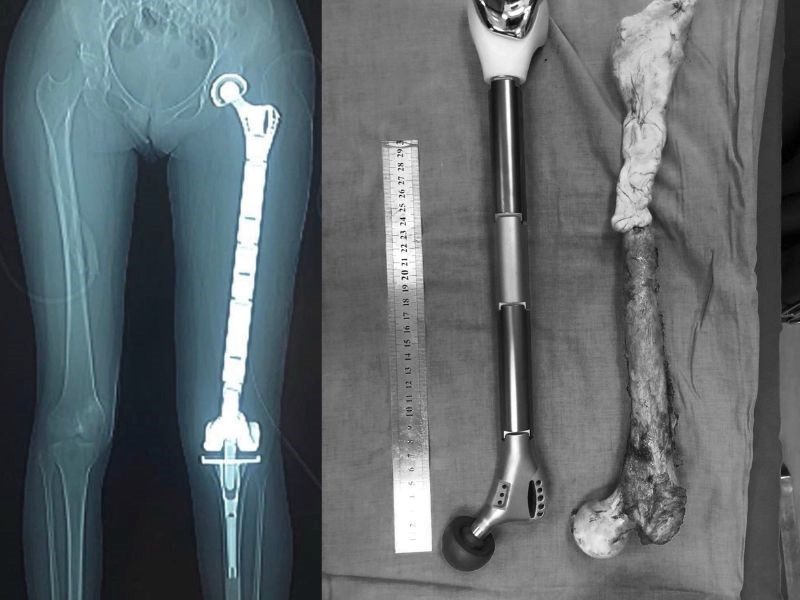

Ung thư xương là căn bệnh nguy hiểm, ảnh hưởng tới sức khỏe và sinh hoạt của người bệnh

Ung thư xương là một bệnh lý ác tính hiếm gặp, hình thành khi các tế bào ung thư phát triển bất thường trong xương hoặc các mô lân cận. Tùy thuộc vào vị trí khởi phát của bệnh, ung thư xương được chia thành hai loại chính: